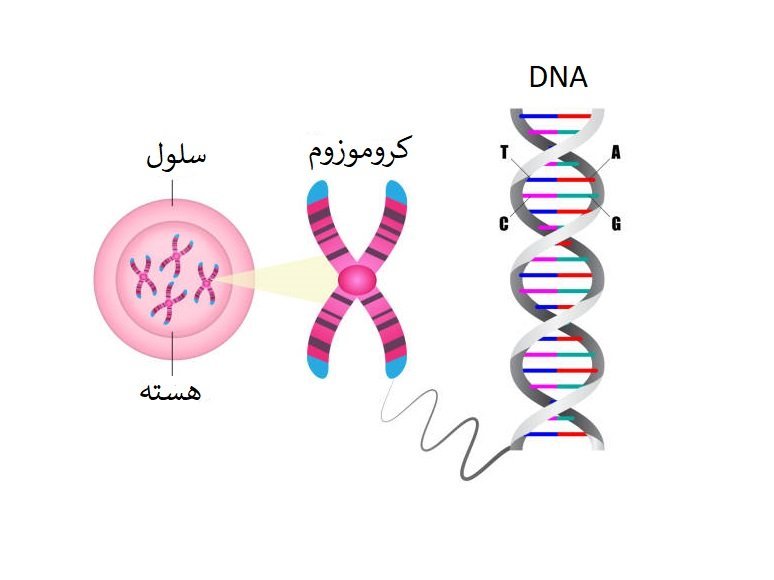

قیمت: 52٬000 تومان - دسته بندی فایل: پاورپوینت

قیمت: 52٬000 تومان - دسته بندی فایل: پاورپوینتپاورپوینت ساختار کروموزوم

فروش ویژه پاور پوینت حرفه ای ساختار کروموزوم با تخفیف استثنایی فقط 55 هزار تومان تعداد اسلاید: 23 اسلاید

قیمت: 78٬000 تومان - دسته بندی فایل: پاورپوینت

قیمت: 78٬000 تومان - دسته بندی فایل: پاورپوینتپاورپوینت ژنتیک جنسیت

فروش ویژه پاورپوینت حرفه ای رژنتیک جنسیت با تخفیف استثنایی فقط 92 هزار تومان تعداد اسلاید: 42 اسلاید